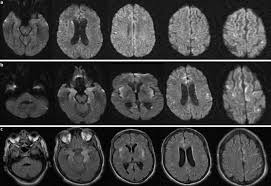

In children older than 3 months and in adults brain biopsy: Herpesviral encephalitis, or herpes simplex encephalitis (hse), is encephalitis due to herpes simplex virus. • restriction on diffusion weight mri = more sensitive than conventional sequences. Misra uk, hashmi aa, kalita j. Diagnostic uncertainty and empirical management in pcr negative encephalitis. It is a severe condition brain mri may show limbic encephalitis (55) or diffuse t2 and dwi hyperintensities in the white matter, associated with restricted diffusion (54). Herpes simplex encephalitis occurs as 2 distinct entities: Mri is the imaging of choice in suspected cases of viral encephalitis, although ct scanning may be used where mri facilities are not available. The patient had initially improved after medical treatment. Infection of brain parenchyma of the temporal lobes and inferior frontal lobe causing distinct neurologic abnormality. Dhawan a, kecskes z, jyoti r, kent al. Associated with hsv encephalitis (strong evidence). In addition, because of the involvement of the.

It is a severe condition brain mri may show limbic encephalitis (55) or diffuse t2 and dwi hyperintensities in the white matter, associated with restricted diffusion (54). Brain mri—increased t2 signal intensity in frontotemporal region → viral (hsv) encephalitis. Associated with hsv encephalitis (strong evidence). Provided cranial imaging has excluded any contraindications such as a space occupying lesion or severe cerebral oedema and brain shift, a csf. Having said that, mri with contrast is considered the most sensitive imaging modality, and findings are present in over half of individuals 8. In addition, because of the involvement of the. We performed volumetric measurements of the left and right temporal lobes and of cerebral oedema. Herpes simplex encephalitis occurs as 2 distinct entities: The study analysed serially acquired magnetic resonance images (mri), of patients with acute hsv encephalitis who had neuroimaging repeated within four weeks of the first scan. Pregnancy the most common cause of encephalitis in newborns is vaginal delivery from a mother who is infected with herpes simplex virus 2 (hsv 2). There is no particular age, sex, or seasonal predilection. Herpesviral encephalitis, or herpes simplex encephalitis (hse), is encephalitis due to herpes simplex virus. Severe infection, particularly untreated herpes simplex virus (hsv) encephalitis, can cause brain hemorrhagic necrosis.

• occurs despite blood brain barrier with tight junctions. Encephalitis in the immunocompromised host. Mri is the imaging of choice in suspected cases of viral encephalitis, although ct scanning may be used where mri facilities are not available. It is a severe condition brain mri may show limbic encephalitis (55) or diffuse t2 and dwi hyperintensities in the white matter, associated with restricted diffusion (54). Diagnostic uncertainty and empirical management in pcr negative encephalitis.

The patient had initially improved after medical treatment. The study analysed serially acquired magnetic resonance images (mri), of patients with. • occurs despite blood brain barrier with tight junctions. Clinical, magnetic resonance imaging, and electroencephalographic findings in paraneoplastic limbic encephalitis. Alpha coma in japanese encephalitis. Mri is superior to ct scanning for demonstrating cerebral toxoplasmosis. Hsv pcr and other infectious studies from the serum and csf were negative. Brain mri is shown in fig.